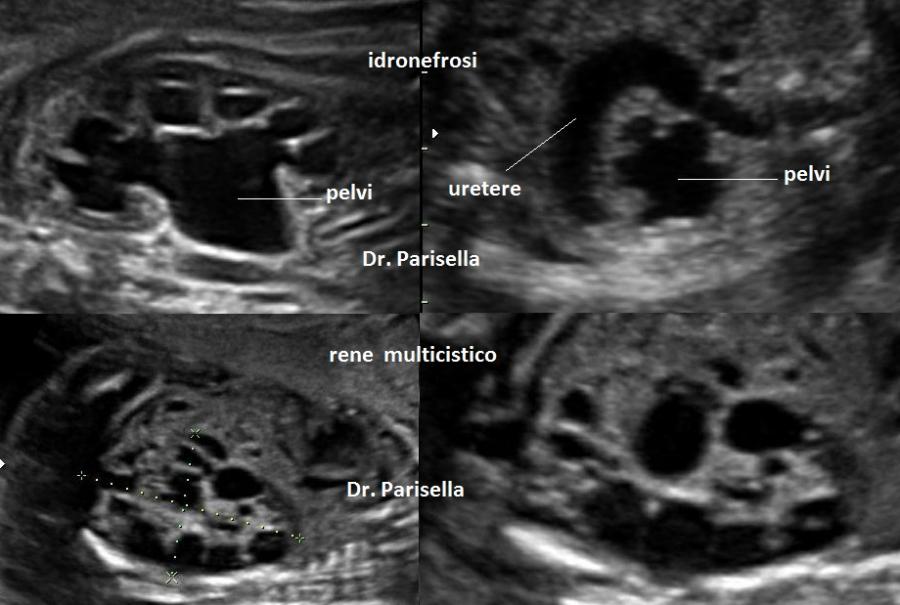

anomalie renali (Reni Policistici, Idronefrosi,...)

R) anomalie Renali: displasia, idronefrosi, ectopia

4) anomalie renali (agenesia, idronefrosi);